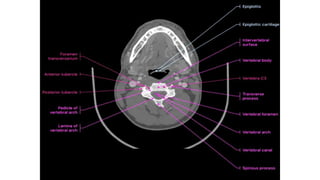

Normal Spinal canal diameters

CERVICAL SPINE

At the cervical levels C4–C7 the average antero-

posterior diameter is 17 mm and values below 14 mm

are considered critical.

At the lumbar level a classification of spinal stenosis was

suggested by Benoist:

• Severe stenosis (< 10 mm)

• Moderate stenosis (10–12 mm)

• Mild stenosis (12–14 mm)

Normal Spinal canaldiameters THORACIC SPINE CERVICAL SPINE

At the cervicallevels C4–C7 the average antero- posterior diameter is 17 mm and values below 14 mm are considered critical. At the lumbar level a classification of spinal stenosis was suggested by Benoist: • Severe stenosis (< 10 mm) • Moderate stenosis (10–12 mm) • Mild stenosis (12–14 mm)